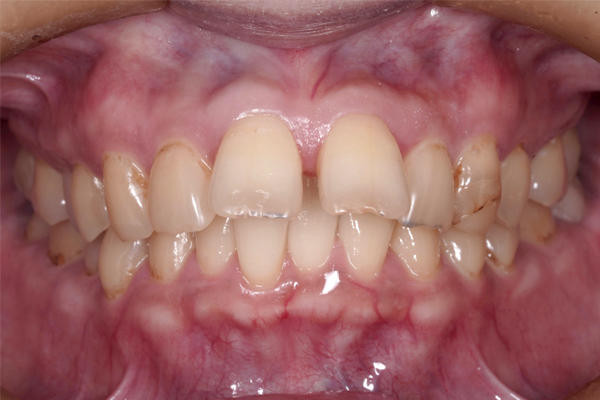

正面の比較

この症例のポイントとして、患者さまは長年、前歯が出ていることや隙間があることを気にされていました。ワイヤー矯正でもインビザラインでも構わないので、しっかり治療したいというご希望がありましたが、通院間隔をできるだけ延ばしたいという点から、今回はインビザラインによる矯正治療を選択しています。

治療開始から9か月が経過し、前歯の重なりは徐々に改善し、上の前歯も少しずつ後方へ移動しています。見た目にも変化が現れはじめており、治療は順調に進んでいます。

本治療では、インビザラインを用いた非抜歯矯正を行っています。治療の進行にあわせて、インプラントアンカーを使用し、歯を後方へ移動させる計画です。治療期間はおよそ1年6か月を予定しており、現在は開始から9か月が経過した段階です。